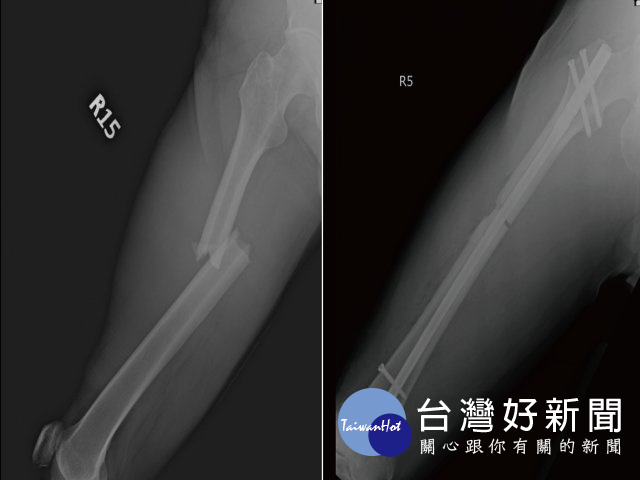

光田綜合醫院骨科王稚暉表示,王先生送抵急診檢查發現他三肋骨骨折、右腿股骨骨折、肝撕裂傷,合併有腹腔出血的狀況,院方當時緊急召集急診、一般外科、胸腔外科及骨科醫師共同治療下,手術縫合額頭傷口、股骨微創骨折復位固定,並給予輸液、輸血,病況始穩定下來。然考量飛機艙壓,王先生接受醫師建議在台灣多停留休養一周,讓身體有更多時間復原後再搭飛機返國。